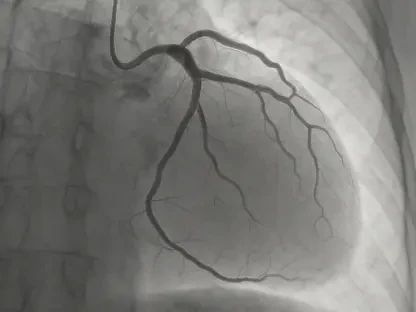

For clinical software, the changes are just as profound. An AI tool that analyzes a radiologist’s written report to generate a diagnostic summary is now considered a non-device, falling outside the FDA’s purview. In contrast, software that directly analyzes the medical image itself to produce that report remains a regulated medical device. Similarly, software predicting a patient’s long-term cardiovascular risk based on standard inputs like age and blood pressure is now exempt. Yet, an algorithm that predicts an imminent risk or uses complex, non-standard data like genomics would still require strict regulatory oversight, highlighting the agency’s focus on risk level and data complexity.